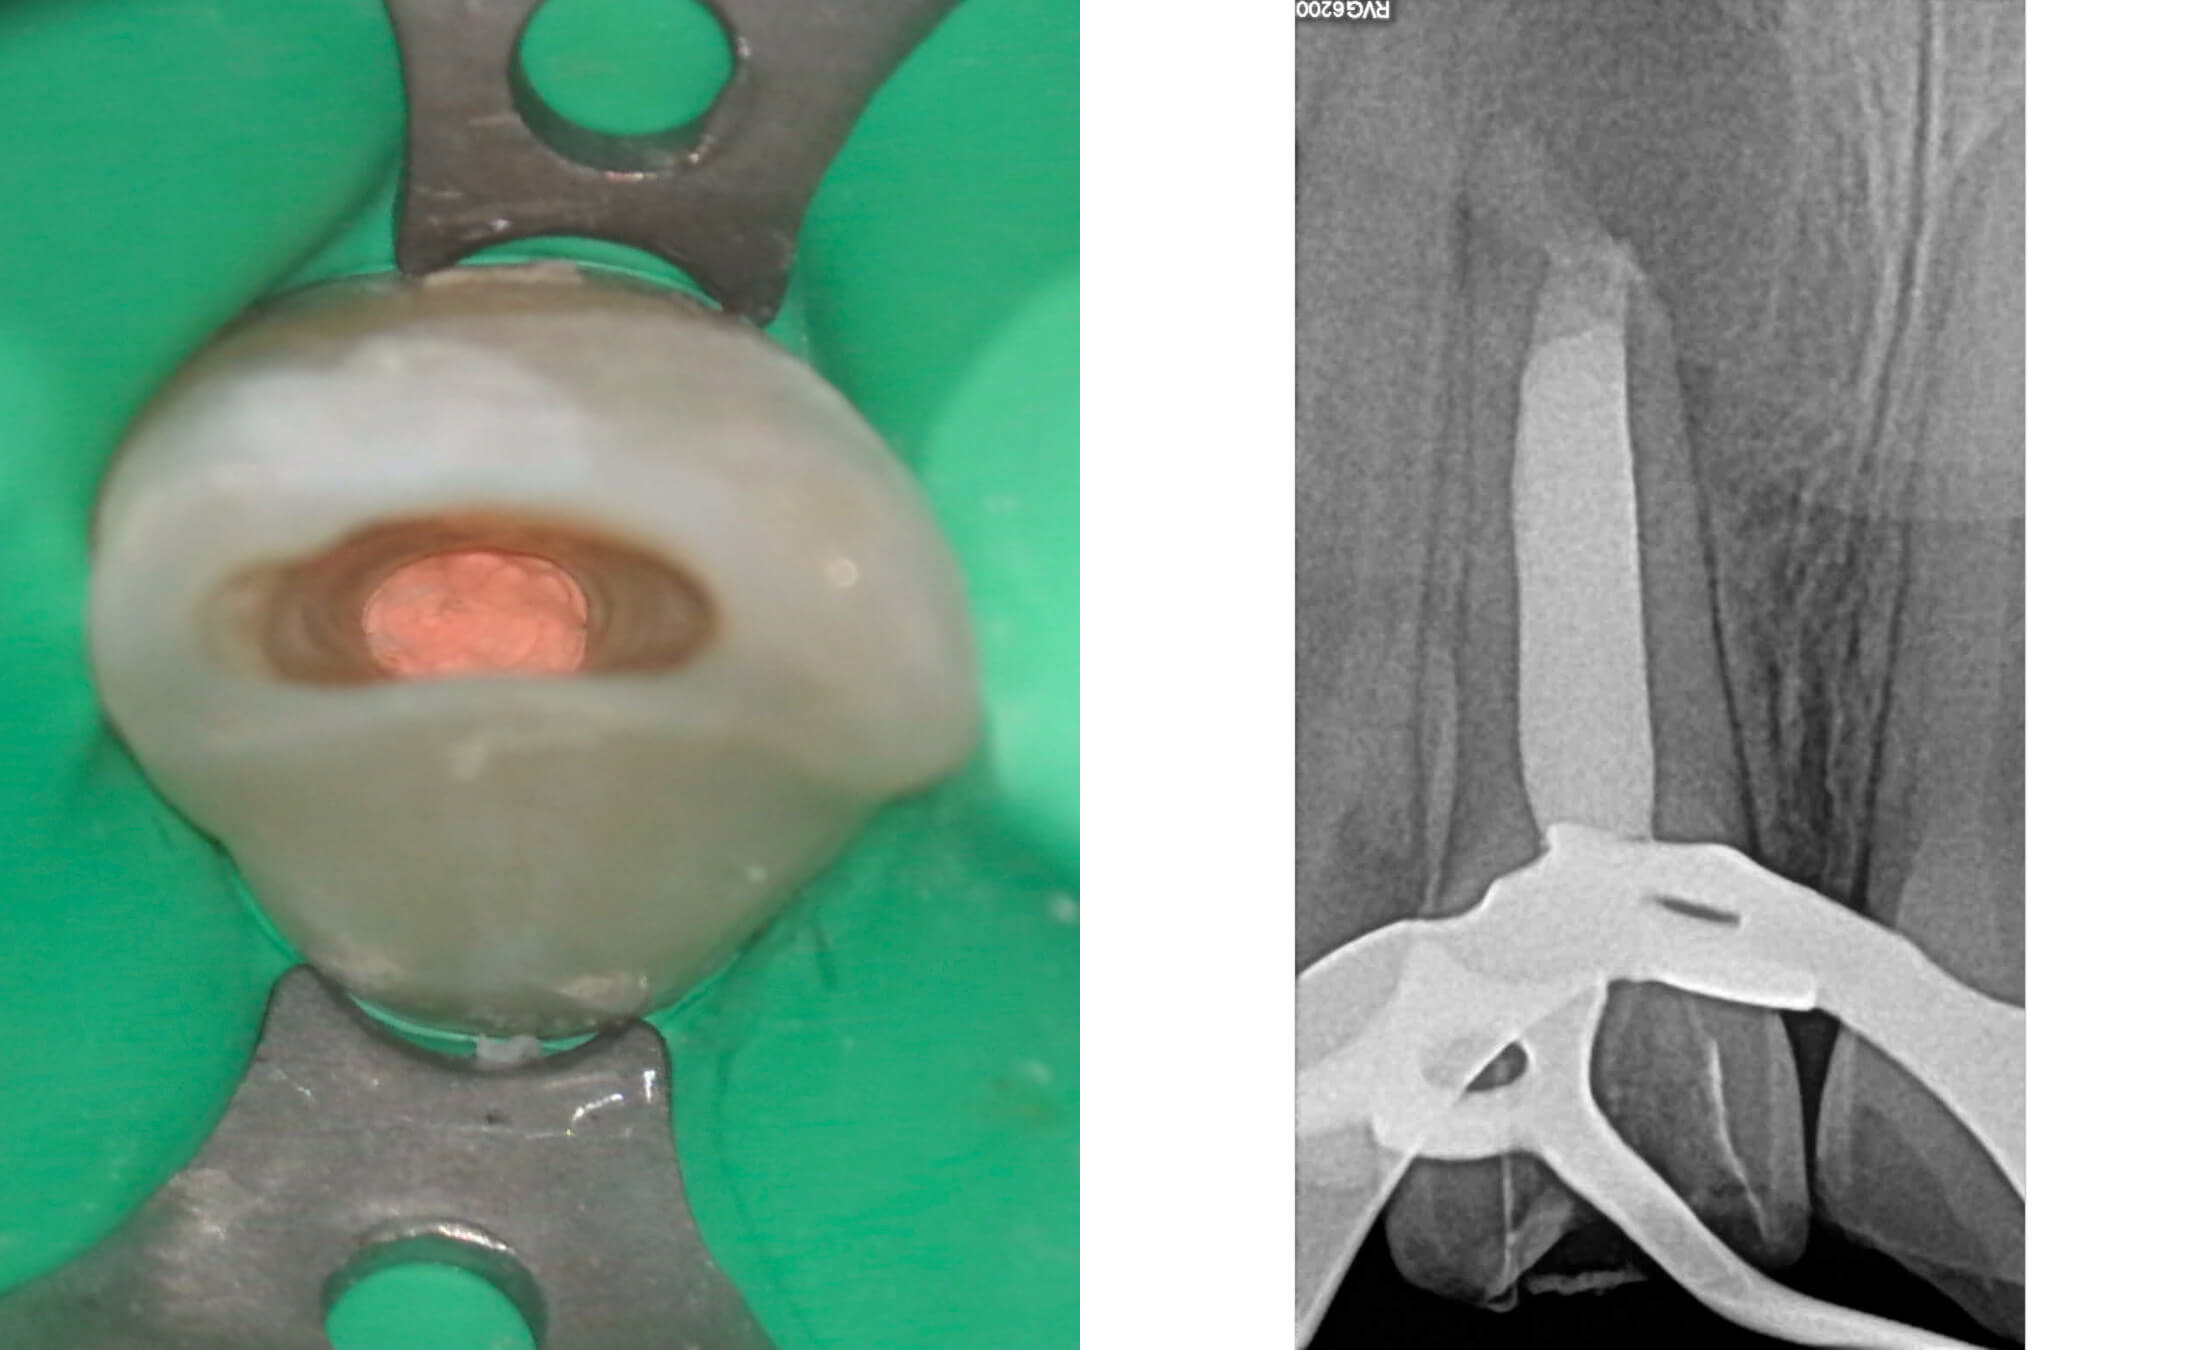

3. During the initial appointment, an endodontic access cavity was prepared, followed by chemo-mechanical debridement of the root canal system using non-instrumentation techniques. The canal underwent thorough irrigation with sodium hypochlorite and EDTA solutions, after which it was temporarily obturated with a calcium hydroxide-based medicament for a two-week period to promote disinfection and periapical healing. (Image 5,6)